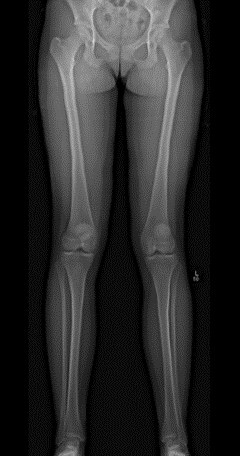

Risk factors for recurrent patellar instability have been well documented. However, data from JUPITER has identified that patella alta (CDI > 1.2) may be protective against osteochondral fractures if recurrent patellar instability occurs while a TT-TG of > 13 mm is a risk factor.

There are a number of factors that can lead to patellar instability. These factors include alignment, bony anatomy, and soft tissue deficits. We are studying the interactions of these risk factors so that surgeons can better address the underlying pathology.